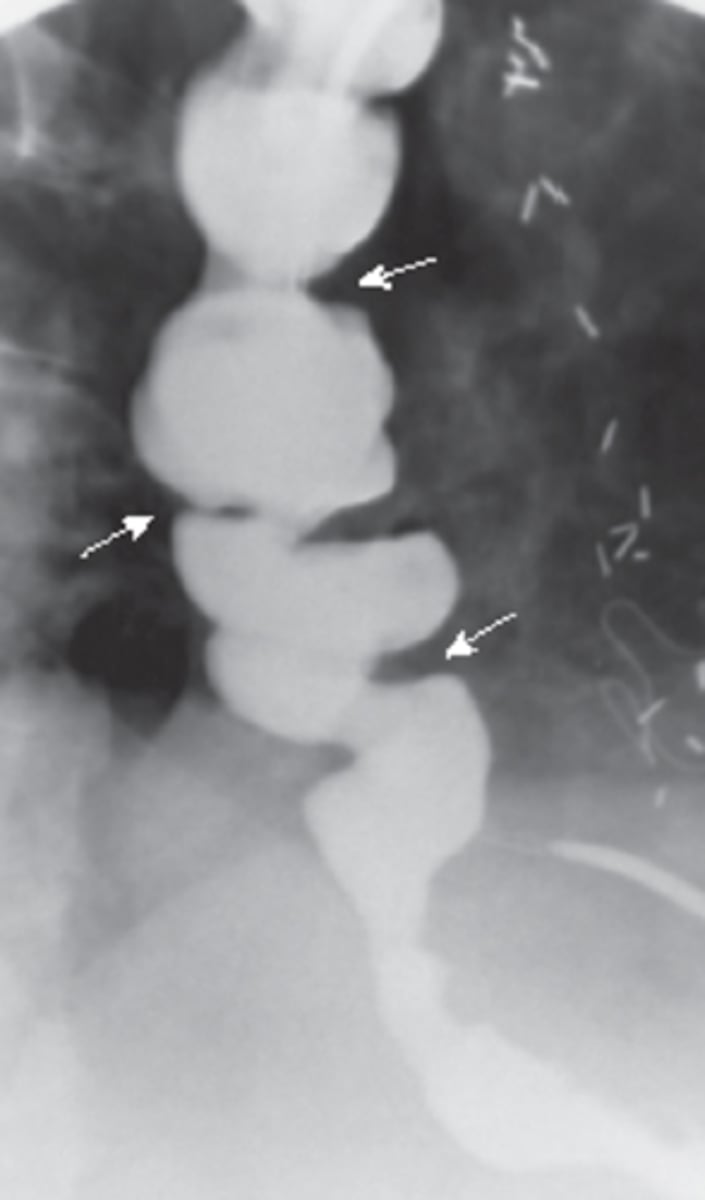

string of pearls sign- diagnostic of mechanical obstruction

stretch sign- small pockets of gas trapped bn valvulae conniventes within fluid filled bowel